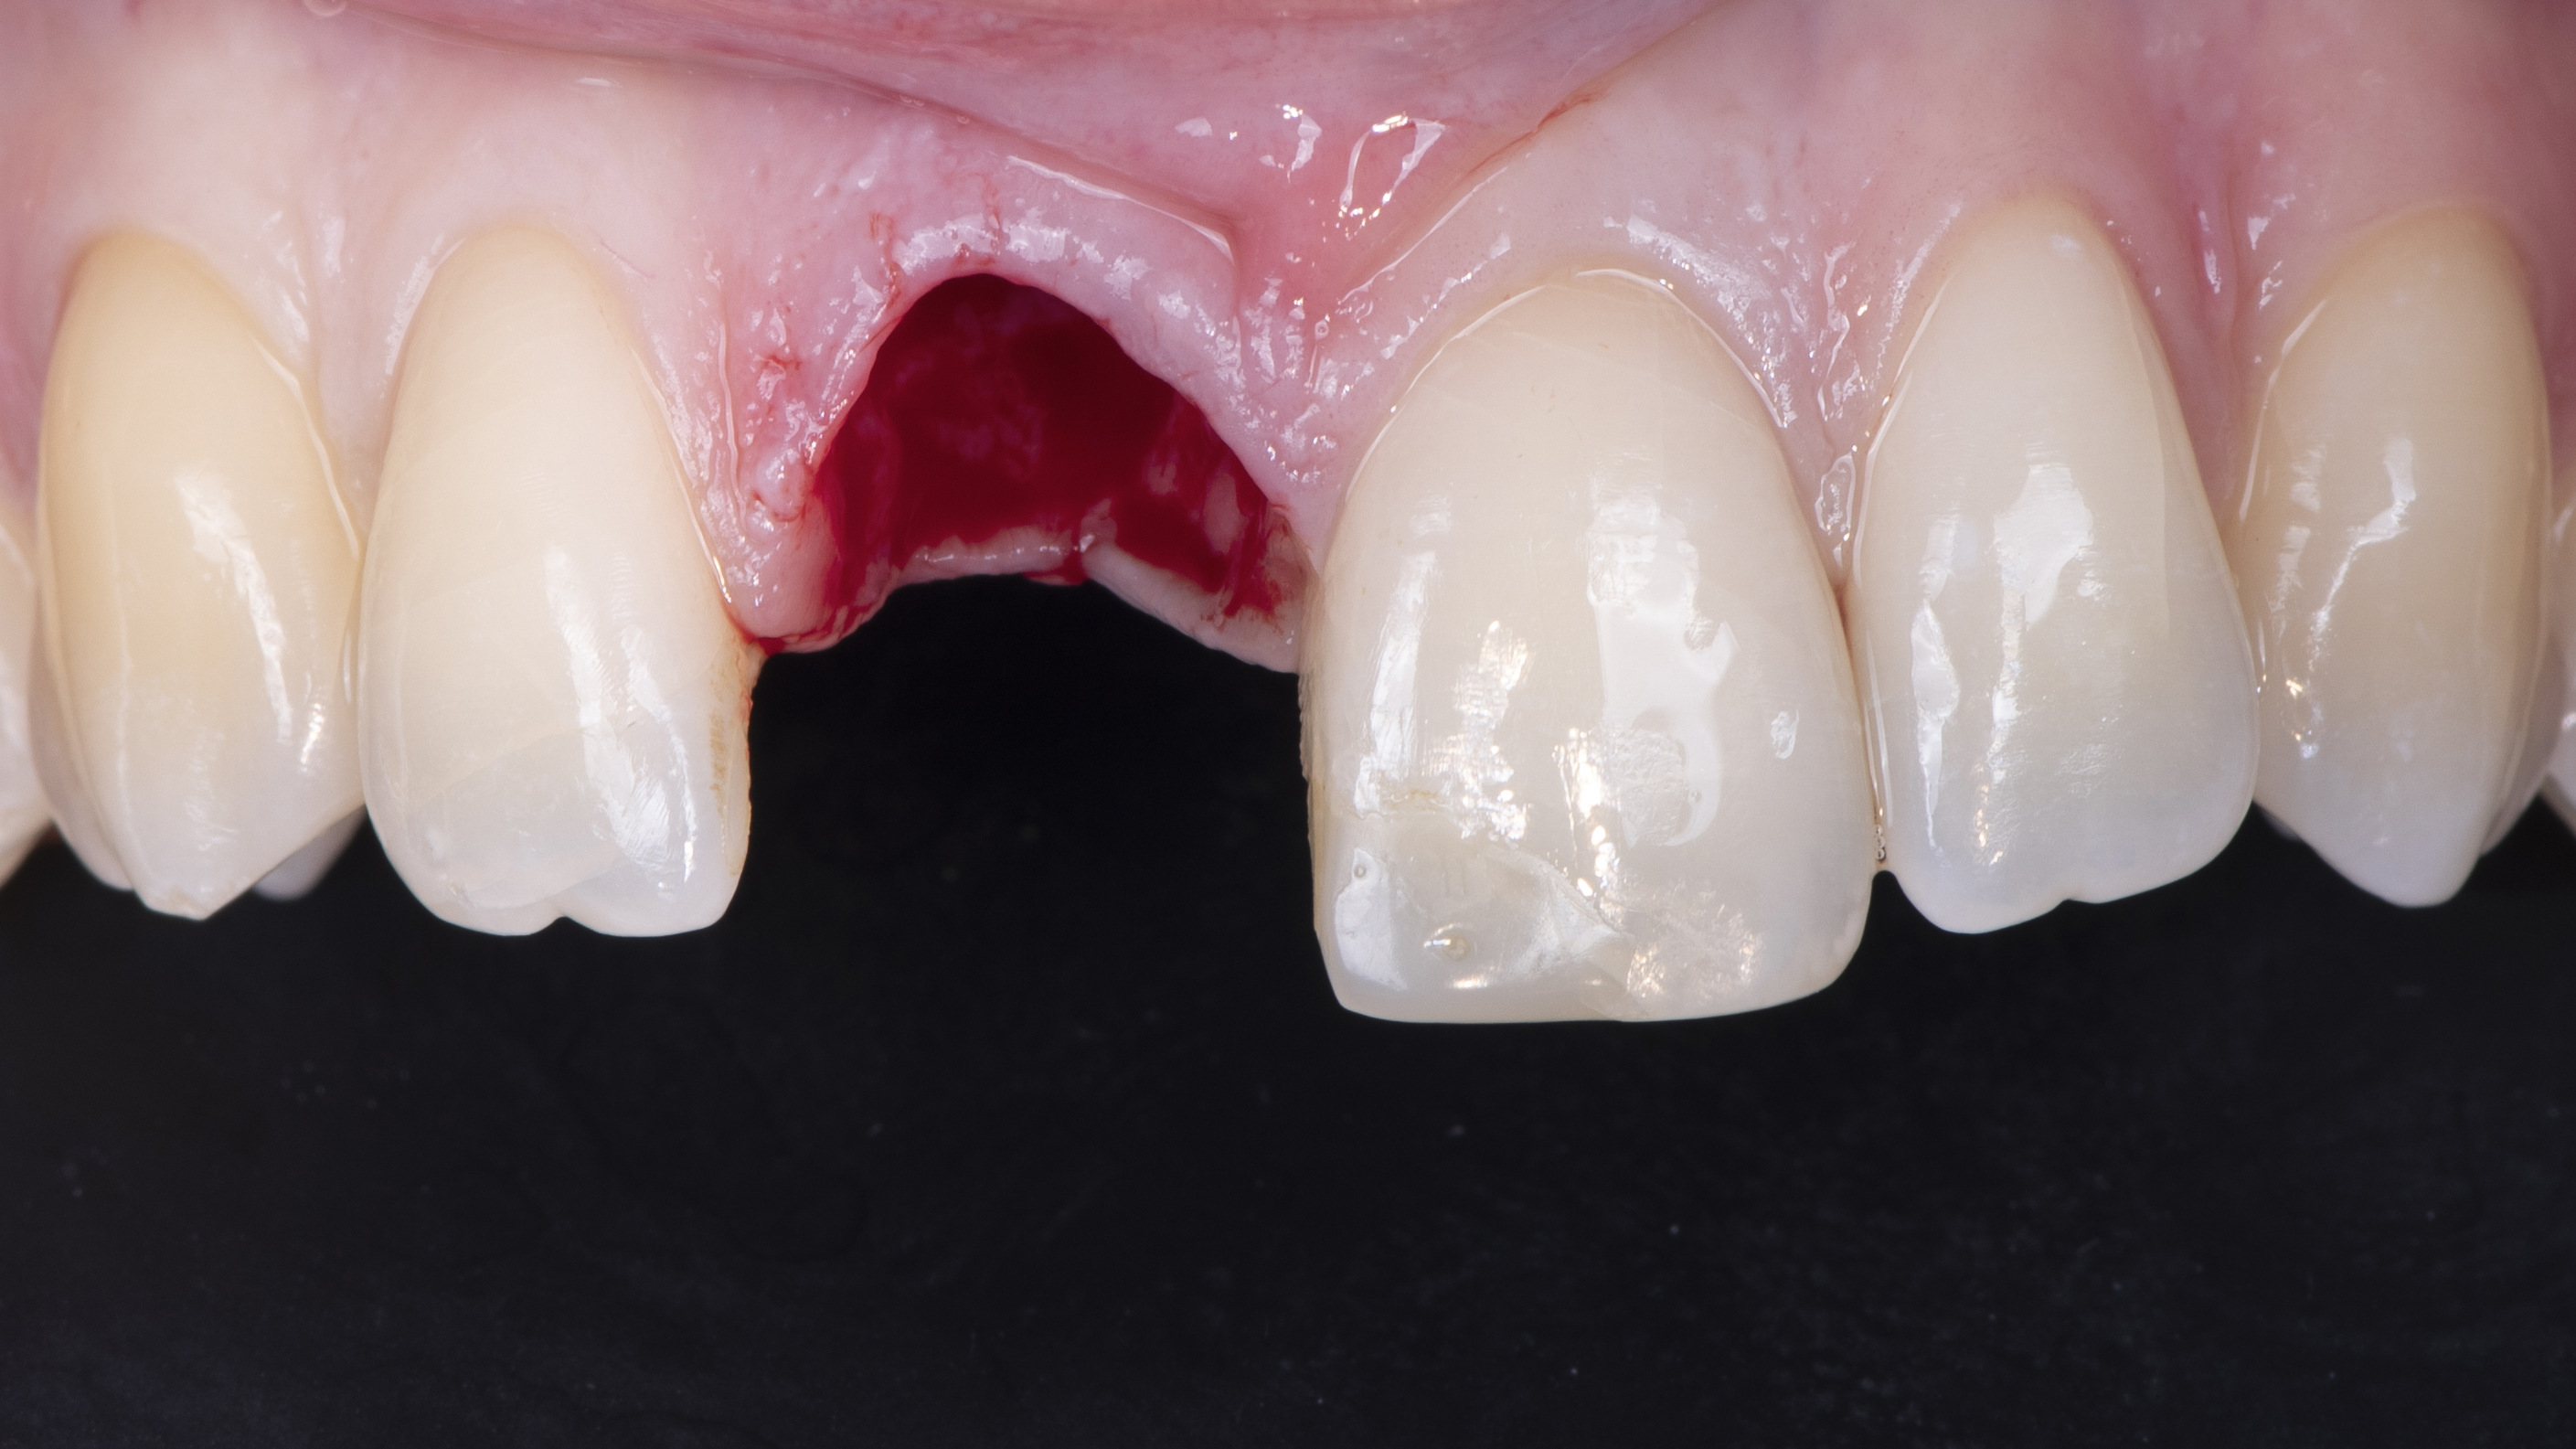

Extraction de la dent la plus atraumatique possible (Photo 10).

Une copie de la couronne de la patiente est imprimée et évidée pour permettre de la positionner correctement. Elle est ensuite solidarisée à un pilier provisoire vissé dans l’implant. Ceci nous permet ensuite d’ajuster le profil d’émergence (Photo 12).